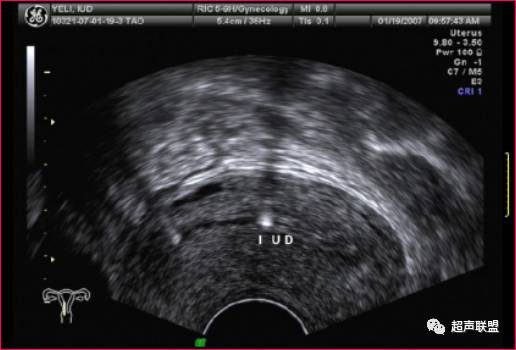

二维超声检查虽可显示IUD与子宫的关系,但易受操作者技术等主观因素的影响,且因为是手动扫描,图像比较粗糙,多只能显示IUD某一局部,研究表明仅有36%可较完整地在一个平面显示IUD,尤其对开放型IUD两横臂的情况不能很好地显示。

(经阴道超声)

由于宫内节育器的形状、质地不同,其超声表现不尽相同。金属圆环和宫形环在二维超声扫查子宫纵切面表现为宫腔内两个分离的强回声,在其后方,由于产生多次反射形成慧尾征。T形环在子宫纵切面显示为宫腔内线状或串珠状强回声,横切面在宫腔底部显示条形强回声,塑料节育器在不同的切面扫查进表现为宫腔内强回声,其后方不伴慧尾征。